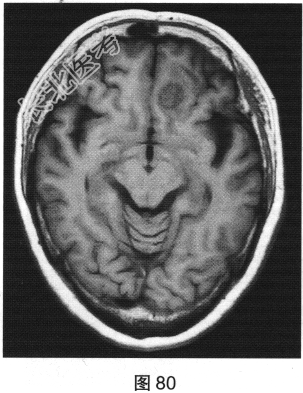

- 多项选择题2.[提示]患者行MRI检查,如图80~图85所示。患者MRI检查的阳性影像学表现包括( )

A、MRI示右侧大片水肿

C、MRI示左侧大片水肿

D、FLAIR呈稍高信号

F、FLAIR呈稍低信号

G、MRI示左侧异常信号影

H、MRI示右侧异常信号影